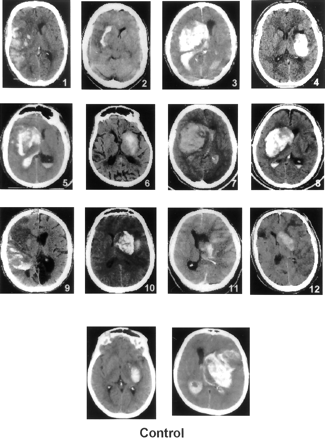

出血症状发生在110年的12个病人(10.9%)接受r-proUK和64年的两个(3.1%)接受静脉注射肝素。这种差异不显著(p= 0.086;相对危险度(RR) 3.5;95%可信区间,0.8 - 31.5)。这些14的CT扫描我的实例所示图2。r-proUK-treated病人的出血与两大支流出血性梗塞(例1、9和11)或大型深半球血肿(例3至8和10),而其他人则相对较小的出血性区域内大型hypodense水肿MCA梗塞分布(例2和12)。所有这些出血发生在前面的梗塞的面积,第一我的症状出现在平均10.2±7.4小时后开始治疗。治疗中风发作的间隔和时间与r-proUK 12出血症状的患者(5.17±0.9小时)不同,剩下的98名患者没有出现出血症状(5.14±0.8小时)。